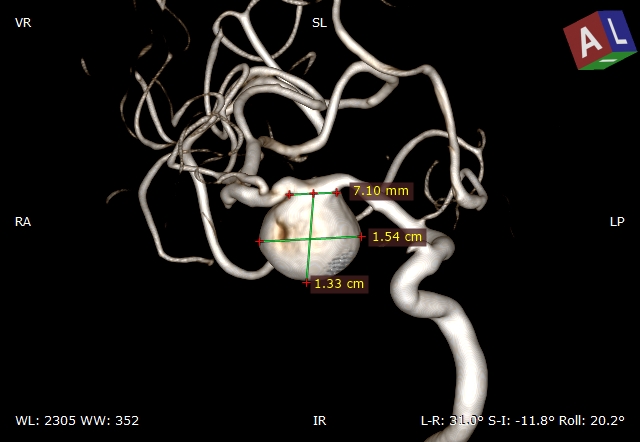

5、急诊查CTA提示:右侧大脑中动脉M1段巨大动脉瘤,和患者家人沟通后送导管室急诊造影。

三维重建提示:右侧大脑中动脉M1段巨大动脉瘤,15.4mm*13.3mm大小,瘤颈7.1mm,近似球形,瘤顶指向下方。